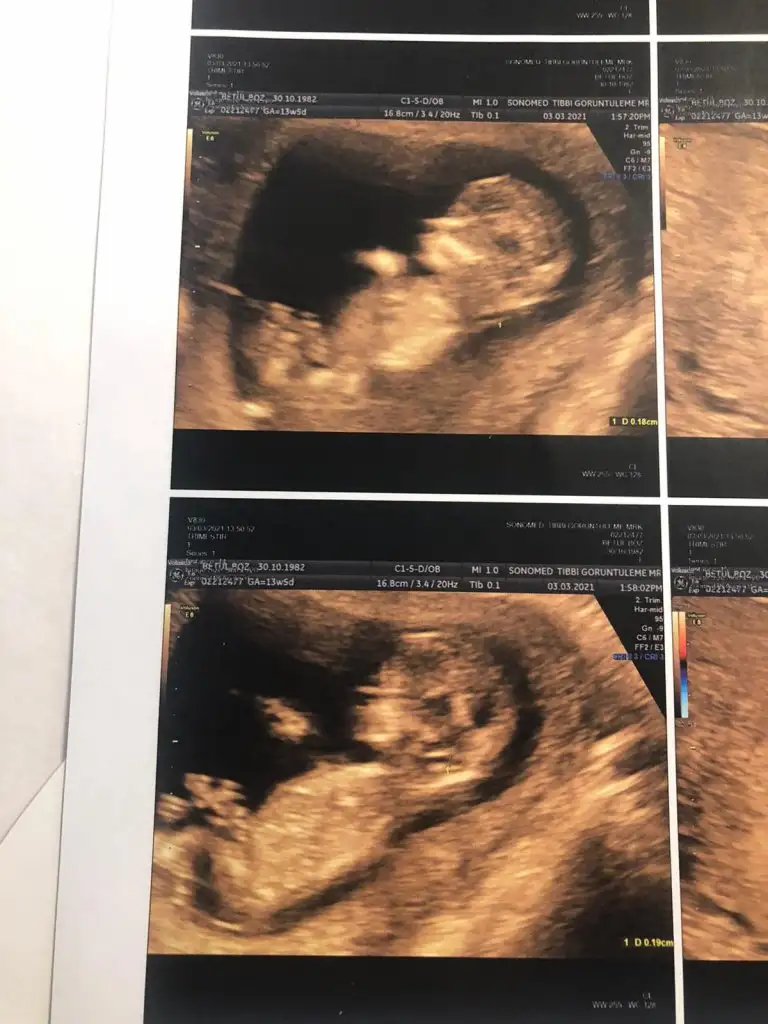

dün 2 li tarama testine girdim bebeğim uyuyordu doktor cinsiyet tahmini yapmadı renkli ultrasonografi görüntülerim var, bu resimlere göre cinsiyet tahmini yapabilirmsiiniz , bu ikinci gebeliğim 8,5 yaşında bir kızım var

tebrik ederim doktor dahil kimsenin göremediğini siz görmüşsünüz 4. aydan sonra anladılar bebeğin erkek olduğunu

Yaaa çok teşekkür ederim 💙😍 sağlıkla gelsin oğlusun 🥰 anketim oylarsaniz sevinirim 🥰